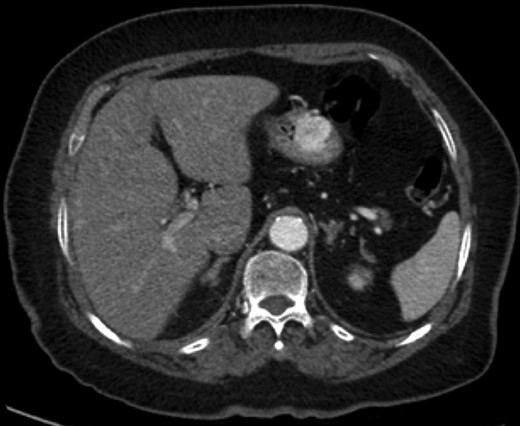

Gastric GT. Note the well-circumscribed submucosal lesion surrounding small vessels (H&E stain, ×20).

Grossly, GTs are multinodular, soft and rubbery on sectioning [3]. The cellular nodules are separated by streaks of gastric smooth muscle, which also surrounds the tumor [3]. Histologic features are central round to oval nuclei with inconspicuous nucleoli and clear to eosinophilic cytoplasm with distinct cell borders [1] (Figs. 3 and 4). GTs are positive for α-smooth muscle actin, vimentin, calponin and caldesmon. They are most often negative for CD117, CD34, chromogranin and synaptophysin [3, 6].